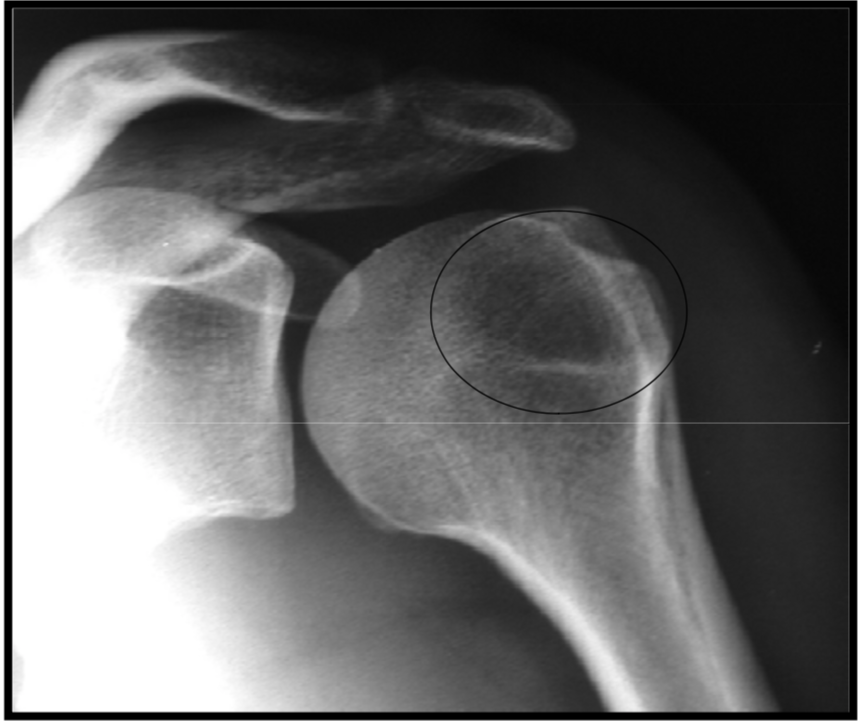

Synovial herniation pit or Pitt’s pit

variation anat normal